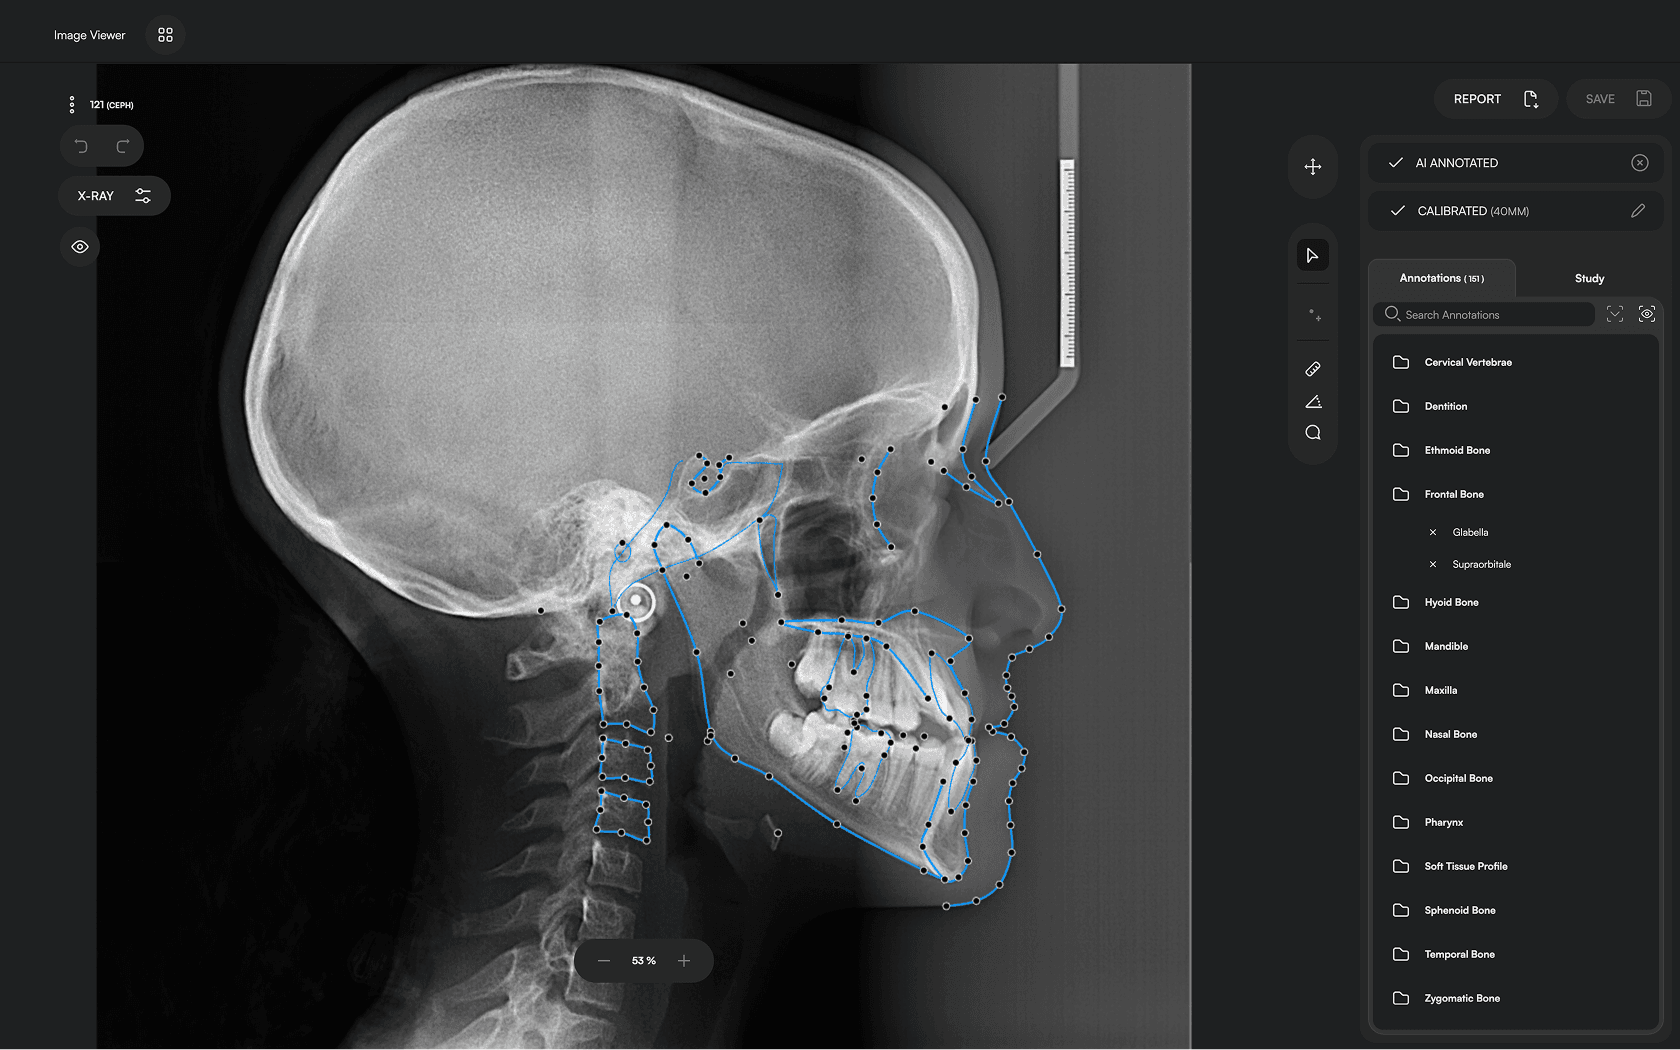

Diverse Analysis

Access automated studies like Steiner and Jefferson to assist in clinical assessment and enhance case evaluations.

Powerful Insights

Experience a comprehensive assessment of skeletal, dental, and soft tissue discrepancies.